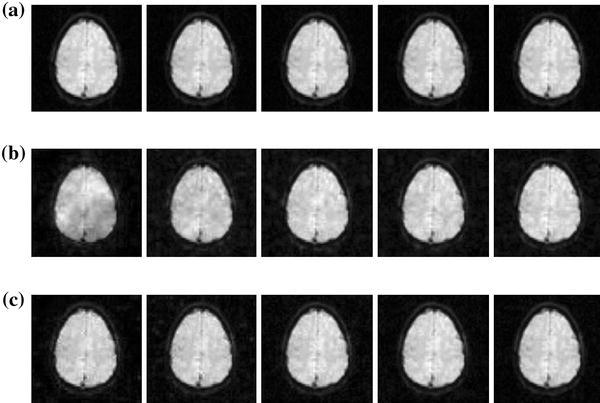

Furthermore, Fig. 6 shows the visually reconstructed results generated by the two methods. The random sampling results in more blurry and noisy functional MR images. Meanwhile, the IMD method is able to provide more detailed functional MR images, which is very important in fMRI techniques (e.g. activity pattern detection).

Fig. 6.

Reconstructions of functional MR images (2nd, 5th, 8th, 11th, 14th frames). a original sequence, b random sampling, c proposed method